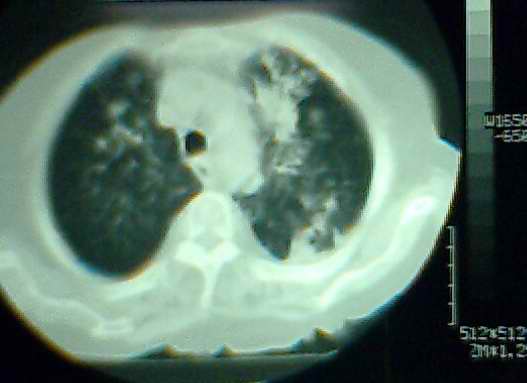

以上是2009-05-25的照片。

以下是引用hhx58在2009-9-11 19:48:00的发言:[br]有4个是心电监护的电极。[br]ct图片可见有肺气囊。但未拿到片上传。

以下是引用37度在2009-9-12 11:54:00的发言:[br][br] [br] 支气管扩张合并混合型感染 [br] [br]

以下是引用dyqct在2009-9-12 8:42:00的发言:[br]慢性支气管炎合并间质纤维化、肺气肿、支气管扩张、感染。建议ct进一步检查。

以下是引用黑白光影在2009-9-12 16:43:00的发言:[br]慢支并感染(霉菌?)